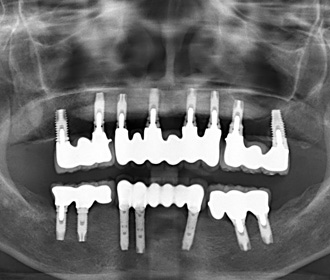

当医院では、アストラインプラント、ZimVieインプラント、Straumannに対応しており、今までの安価なサードパーティー製のものとは一線を画する適合精度、機能性、審美性、破損時の独自の保証システムに基づいて採用しており、良好な臨床実績、成績を得ています。全ての歯牙を失った方でも、全てをインプラント治療で、元々あったご自身の歯牙と全く同じ機能、審美回復できるケース、現在、総入れ歯をご使用中で、その入れ歯にご不満をお持ちの方も、数本のインプラントと入れ歯を組み合わせる治療(インプラントオーバーデンチャー)で格段に機能回復可能なケース、さらに、ブリッジのように歯牙を削らず、単独で処置するケースなど、多彩に応用可能です。

インプラント治療例